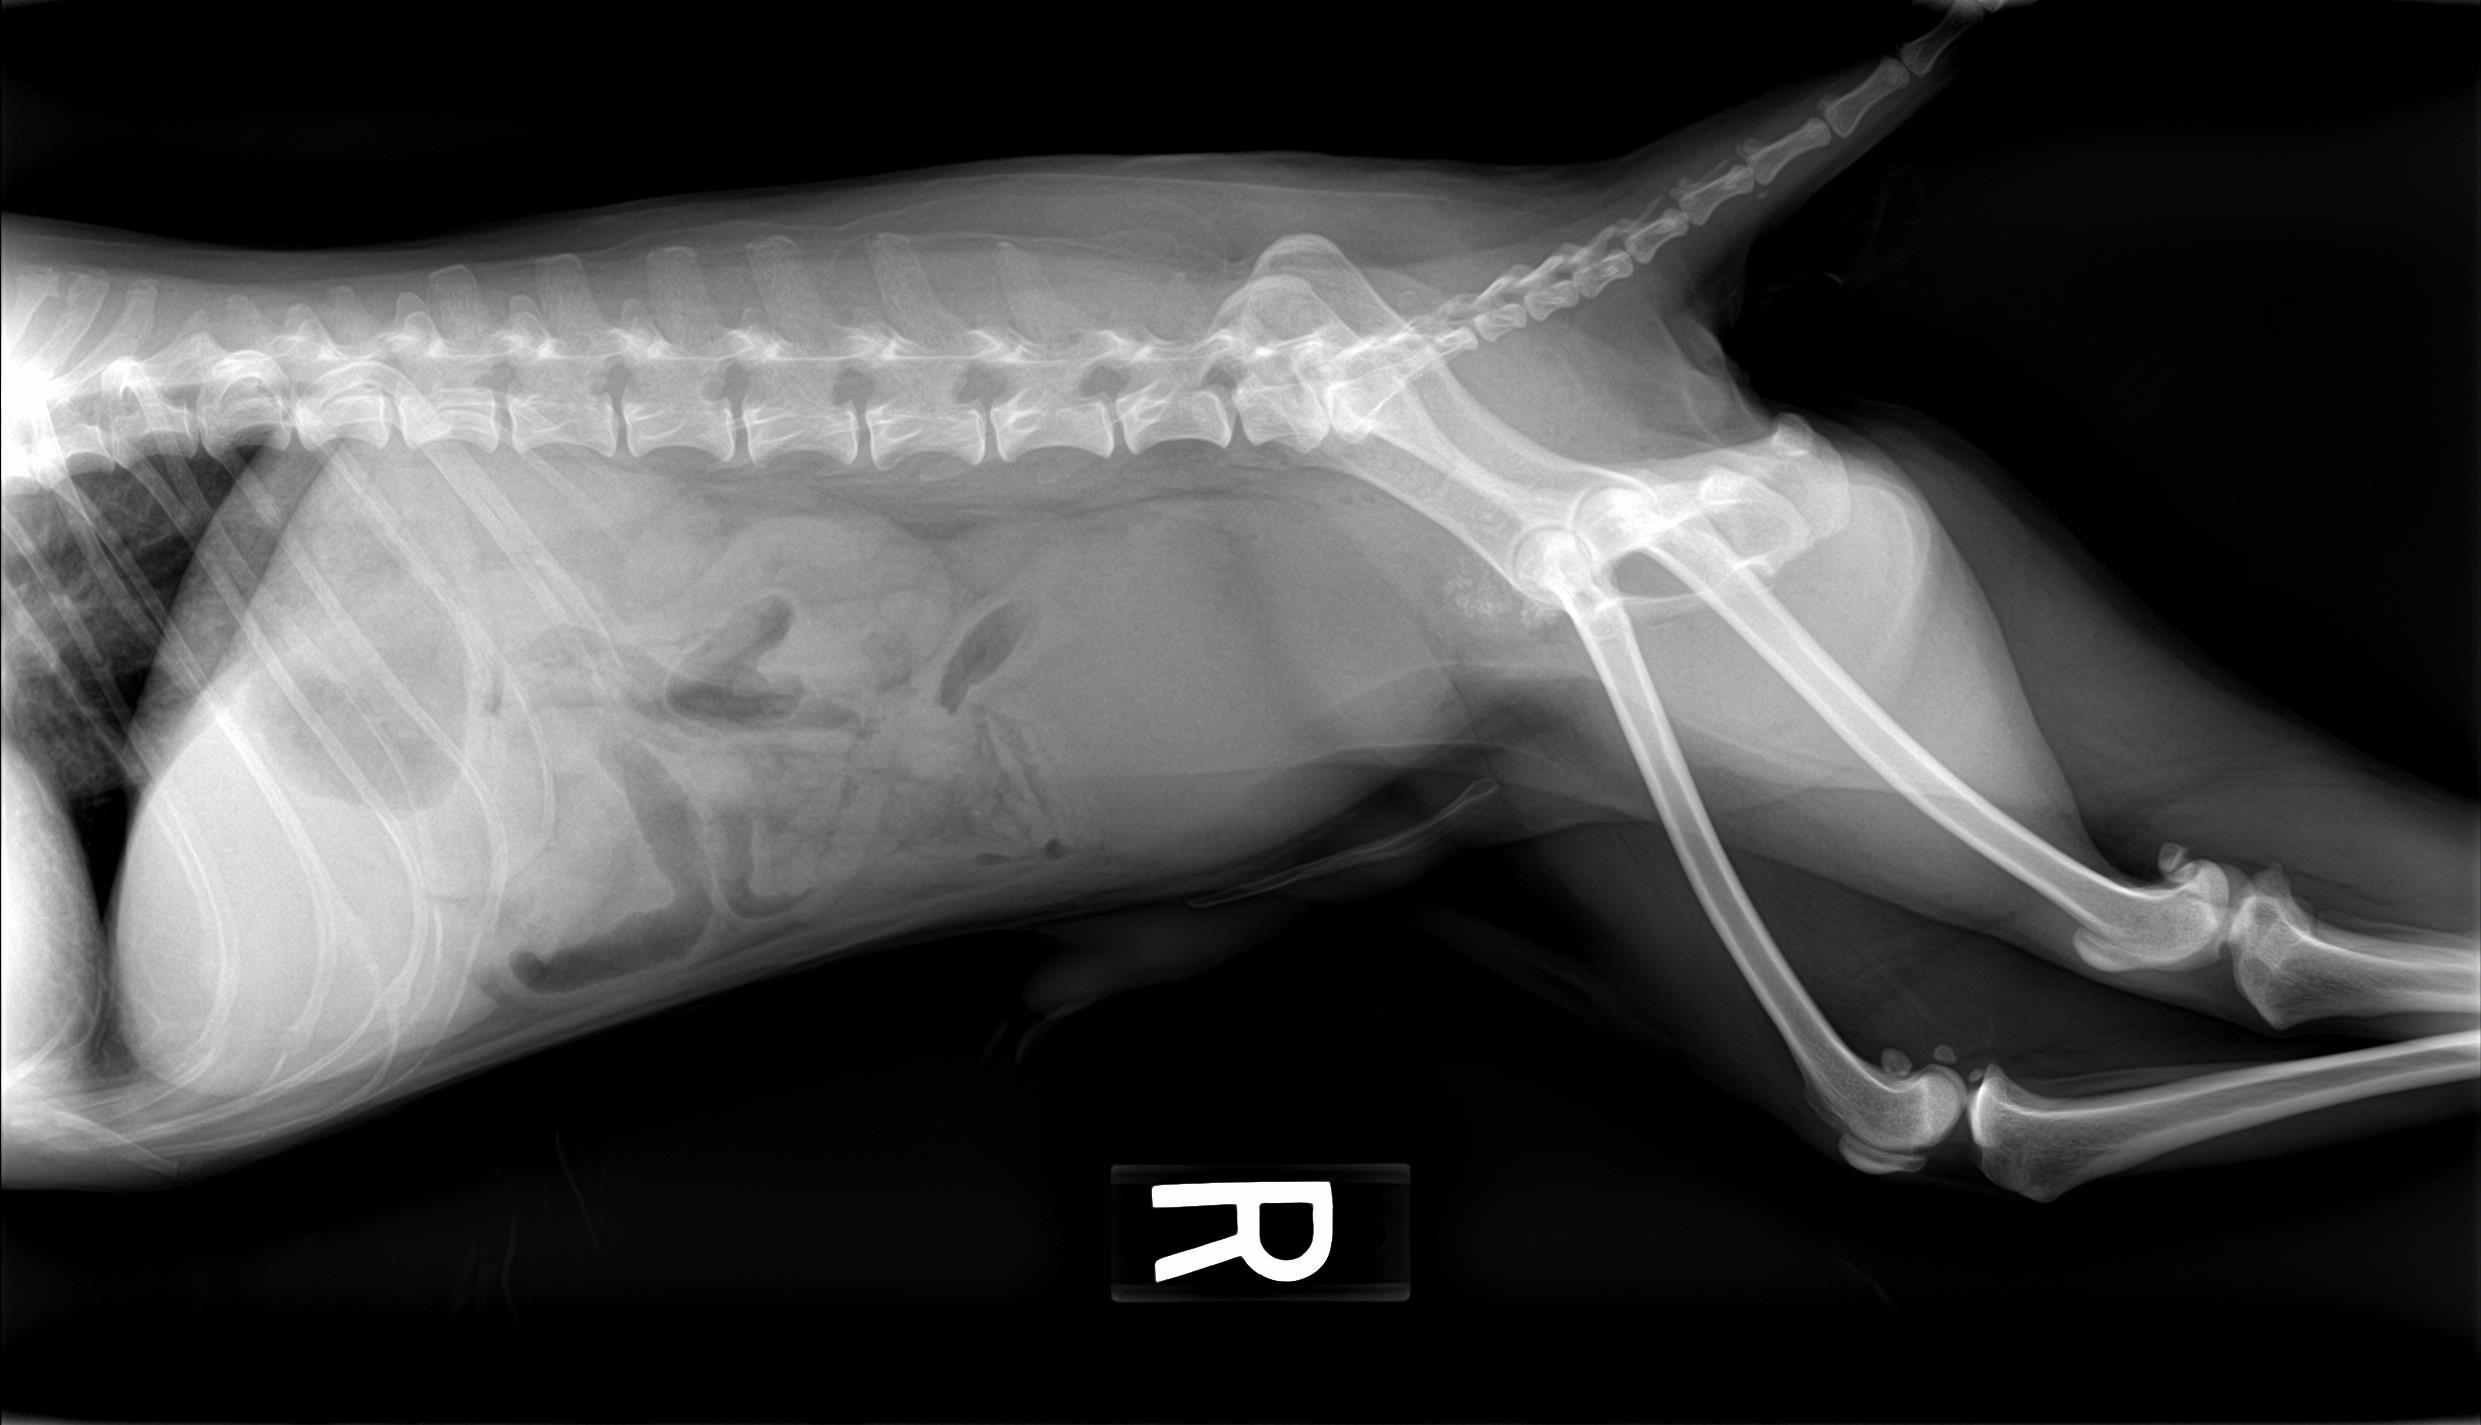

A 14-year-old neutered male Pomeranian dog was presented for evaluation of pollakiuria, diarrhea, inappetence, and lethargy. Abnormalities on physical examination included a painful, enlarged and symmetrical prostate, a very large and firm urinary bladder that could be expressed, and a grade III/VI heart murmur. On survey thoracic radiographs, calcification of the prostate gland was evident.